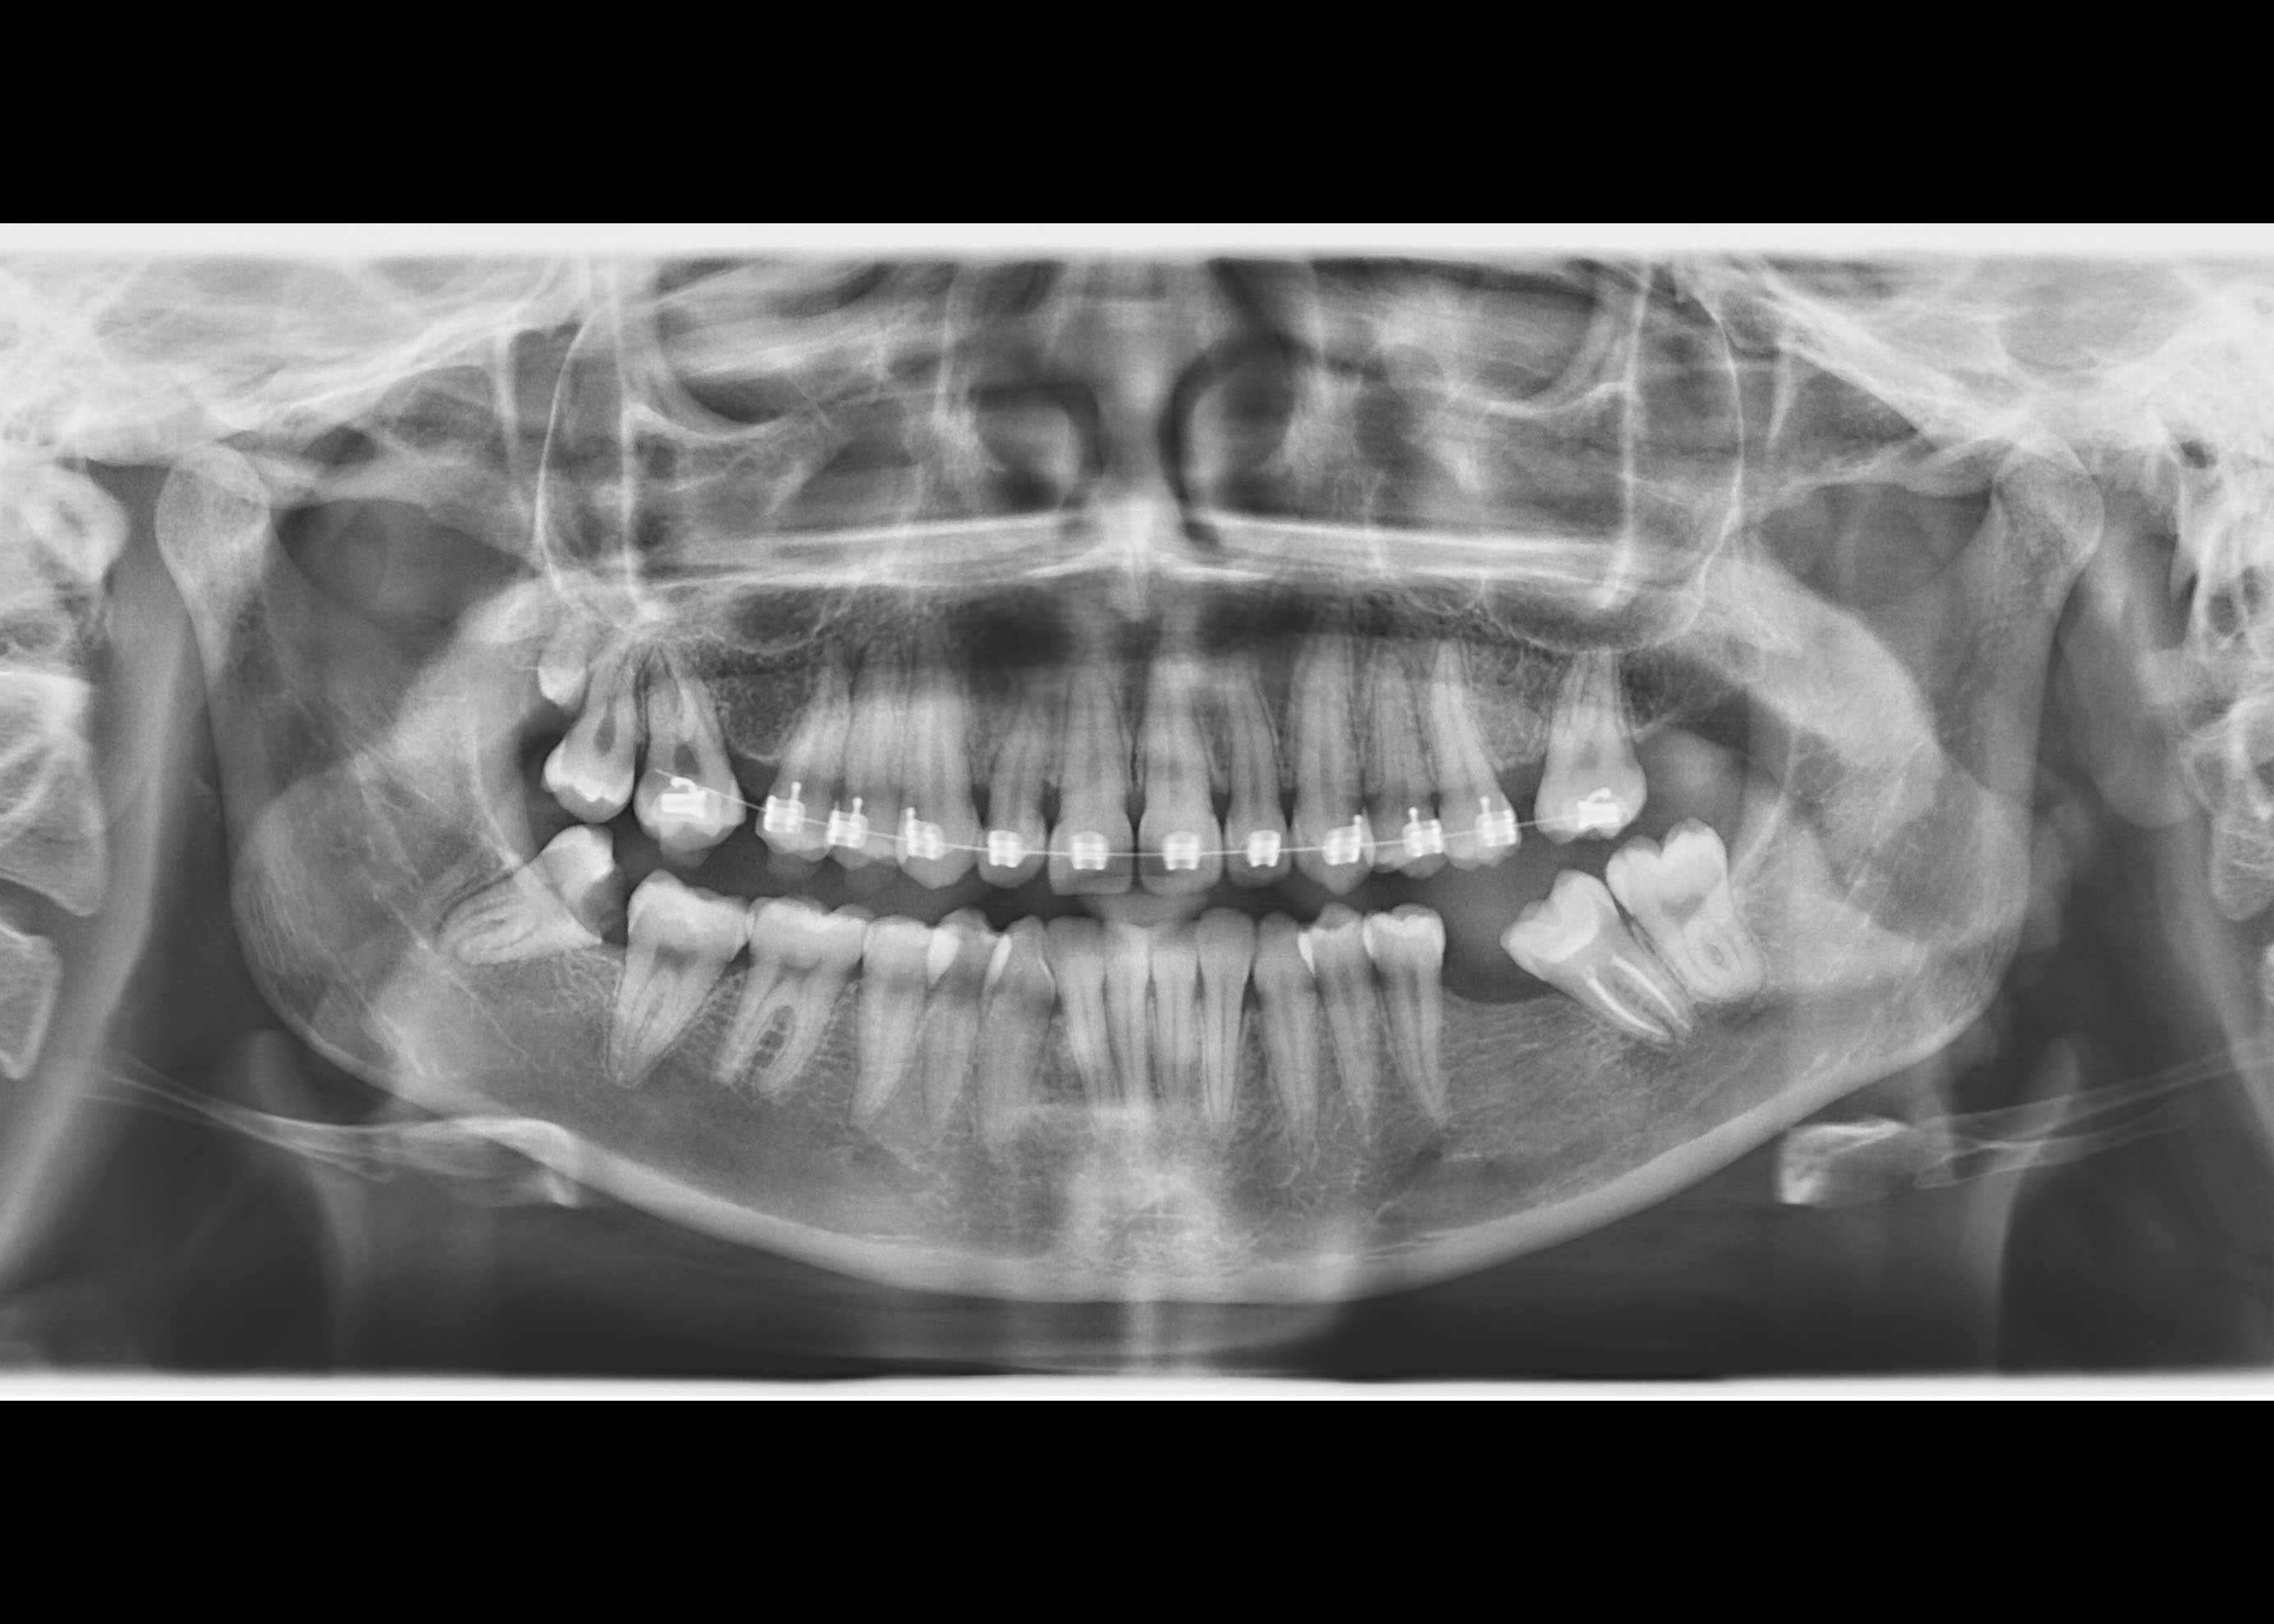

В настоящее время доступны следующие возможности для диагностики:

- Ортопантомографическая рентгенодиагностика;